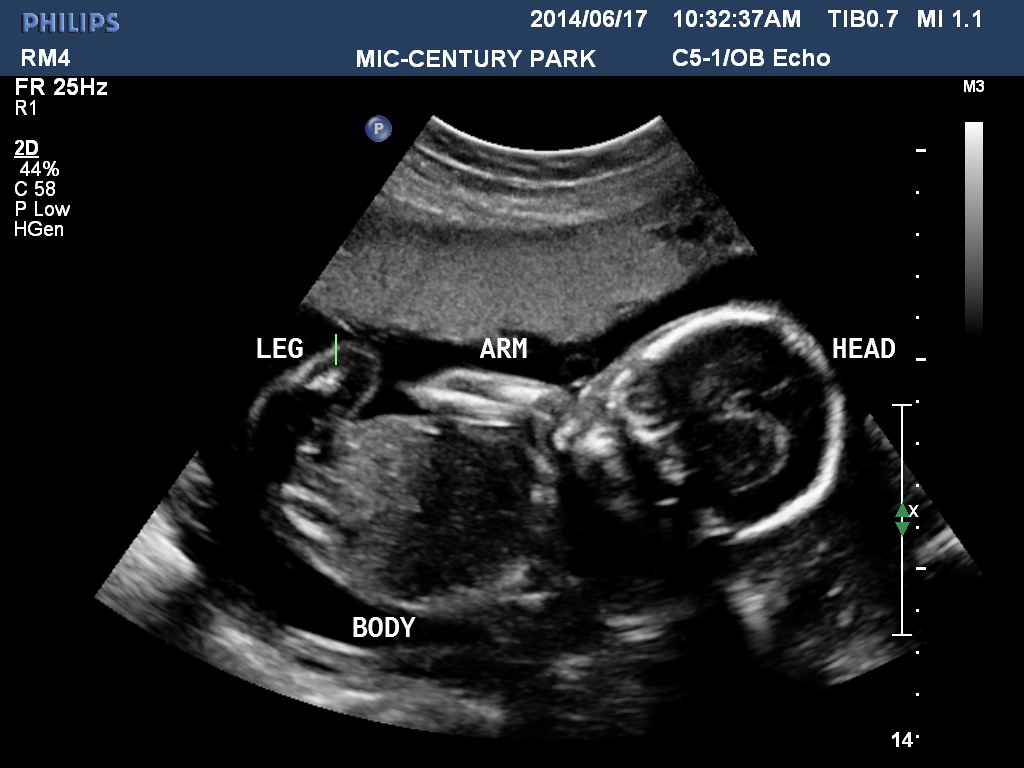

I went for my anatomy scan at 20 w 4 d. I did not ask the tech then about the gender however now i am very anxious! I haven't got that many pics but heres one. Not sure if it will be clear enough.Attachment 19533Attachment 19534